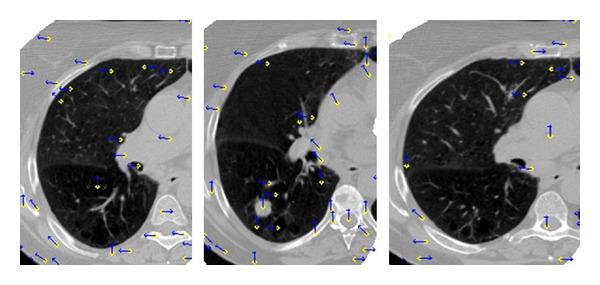

Accurate target delineation of CT image is a critical step in radiotherapy treatment planning. This paper describes a novel strategy for automatic contour propagation, based on deformable registration, for CT images of lung cancer. The proposed strategy starts with a manual-delineated contour in one slice of a 3D CT image. By means of feature-based deformable registration, the initial contour in other slices of the image can be propagated automatically, and then refined by active contour approach. Three algorithms are employed in the strategy: the Speeded-Up Robust Features (SURF), Thin-Plate Spline (TPS), and an adapted active contour (Snake), used to refine and modify the initial contours. Five pulmonary cancer cases with about 400 slices and 1000 contours have been used to verify the proposed strategy. Experiments demonstrate that the proposed strategy can improve the segmentation performance in the pulmonary CT images. Jaccard similarity (JS) mean is about 0.88 and the maximum of Hausdorff distance (HD) is about 90%. In addition, delineation time has been considerably reduced. The proposed feature-based deformable registration method in the automatic contour propagation improves the delineation efficiency significantly.

CT图像的精确靶区勾画是放射治疗计划中的关键步骤。本文描述了一种基于可变形配准的用于肺癌CT图像自动轮廓传播的新策略。所提出的策略从3D CT图像的一个切片中的手动勾画轮廓开始。通过基于特征的可变形配准,图像其他切片中的初始轮廓可以自动传播,然后通过主动轮廓方法进行细化。该策略采用了三种算法:加速鲁棒特征(SURF)、薄板样条(TPS)和一种自适应主动轮廓(Snake),用于细化和修改初始轮廓。使用了五个包含约400个切片和1000个轮廓的肺癌病例来验证所提出的策略。实验表明,所提出的策略可以提高肺部CT图像的分割性能。杰卡德相似度(JS)平均值约为0.88,豪斯多夫距离(HD)最大值约为90%。此外,勾画时间显著减少。所提出的基于特征的可变形配准方法在自动轮廓传播中显著提高了勾画效率。